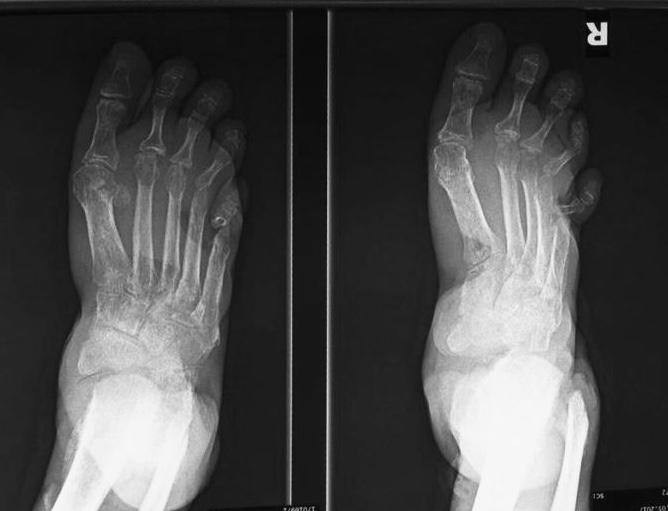

In the presented case there are destruction of talar head and neck with dislocation of talo-navicular joint, resorption of midfoot bones, subchondral sclerosis and multiple subchondral cysts on talocalcaneal aspect and cuboid facet of the calcaneum, progressive decrease of calcaneal inclination with typical rocker-bottom deformity, soft tissue swelling and arterial calcification. Bony debris are seen on dorsal aspect of the foot and posterior ankle joint. All findings are suggestive of Charcot neuro-osteoarthopathy, which is primarily an articular disease and most commonly located in the midfoot.

Osteomyelitis in diabetic foot is infection of the bone that 90% are results from contiguous spread of a skin ulcer. Consequently, the most common location for osteomyelitis is at the pressure points of the forefoot (metatarsal heads, IP joints) and in the hindfoot at the plantar aspect of the posterior calcaneus. Classic triad of osteomyelitis in plain radiograpy are lucencies, periosteal reaction, and bony destruction.

Unlike osteomyelitis, Charcot neuroarthropathy is primarily an articular disease and not related to overlying skin or soft tissue changes. Charcot neuroarthropathy commonly involves multiple midfoot bones. Features include joint instability, dislocation, destruction, disorganization, increased bone density, joint debris and deformity. Presence of subchondral cysts and intraarticular bodies with absence of the secondary signs for osteomyelitis support neuroarthropathy without infection.

In the early stage radiography will not demonstrate bone abnormalities, but MRI will show subchondral bone marrow edema. The subcutaneous soft tissues are not typically involved in Charcot arthropathy.

Osteomyelitis in chronic Charcot is usually located in the midfoot, while osteomyelitis in diabetic neuropathy without Charcot is usually in the forefoot and hindfoot.